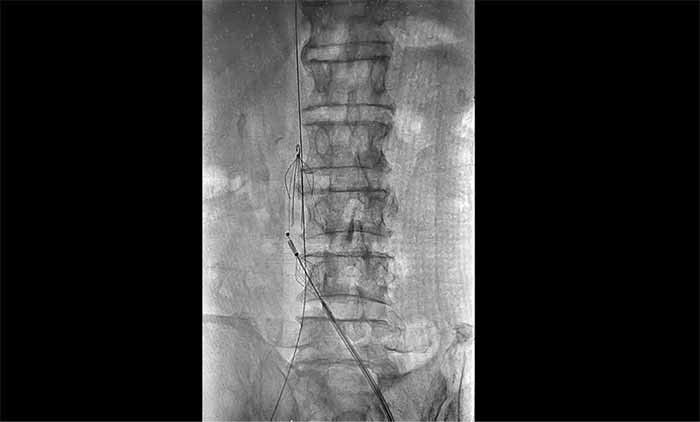

近日,上海蓝十字脑科医院脑血管病科收治了一名脑出血术后长期卧床导致下肢深静脉血栓形成的老年男性患者。患者在外院康复期间发现右下肢严重肿胀,超声提示深静脉血栓,紧急转入本院。

席刚明教授与脑血管病一科4A病区副主任王贵平博士分析指出,下肢深静脉血栓一旦脱落,可随血流引发肺栓塞,危及生命。考虑到患者血栓形成时间较长、抗凝效果不佳,团队决定行介入手术治疗。术后造影显示血栓基本消失,下肢静脉恢复通畅,患者右下肢肿胀明显缓解。

席教授提醒,即便置入滤器,仍需规范抗凝治疗,以预防新血栓形成并降低脱落风险。

▲ 席刚明教授、王贵平博士在为患者手术